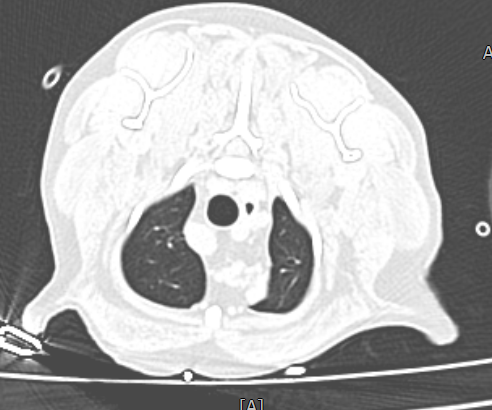

신체검사 및 영상검사 결과, 우측 5번 유선에 종양이 확인되었고, 3~5번 유선이 서로 연결되어 있어 부분 절제 시 재발 위험이 높았습니다. 이에 따라 우측 3~5번 유선 절제술을 계획하였고, 본원 영상진단센터에서 전이 평가를 위해 전신 CT를 촬영하였습니다.

유선종양 CT 결과 / 출처: 24시 온숲동물의료센터

CT 결과, 폐·복부 장기 등 타 장기로의 전이는 확인되지 않았습니다.

이는 유선종양이 국소 부위에 국한된 상태로, 수술을 통한 완전 절제가 가능하다는 판단을 내릴 수 있었습니다.

온숲동물의료센터는 병원 내 자체 CT 장비를 보유하고 있어 유선종양 환자의 전이 평가부터 수술 후 CT 추적관리까지 원스톱으로 진행할 수 있습니다.